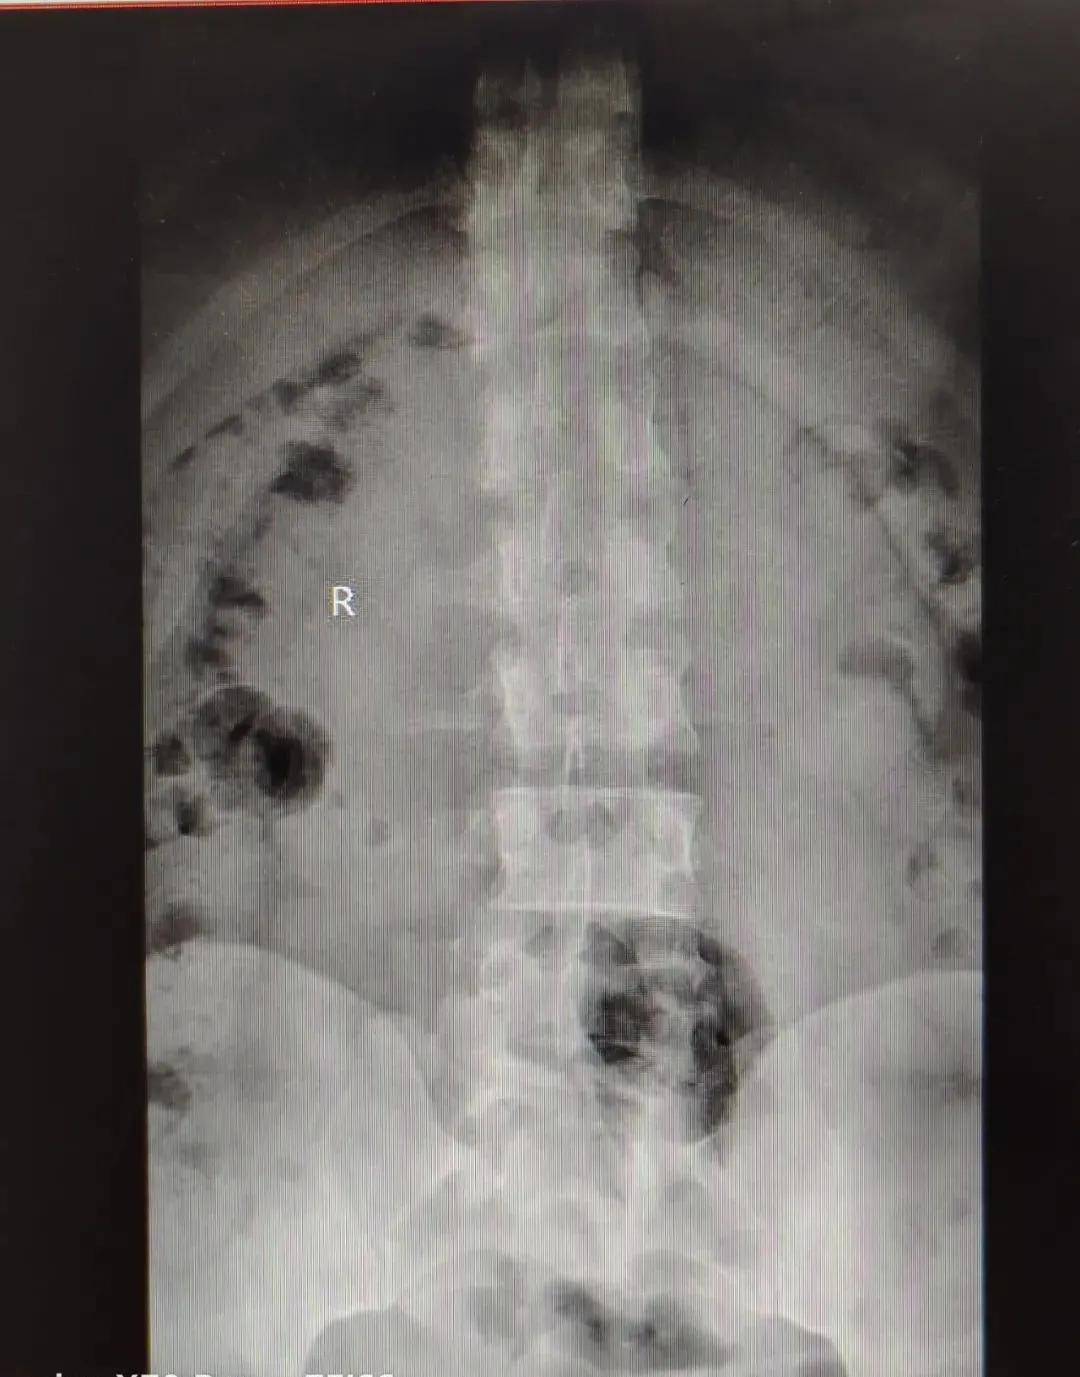

DR检查

DR , 即数字X线成像检查 , 是人体不同组织对X射线的吸收程度 , 呈现不同灰度的图像 。 对软组织的成像效果较差 , 比如肌肉、神经、椎间盘等 , 因此某些情况下不能满足椎间盘疾病诊断的需要 。 但其可以清楚的观察脊柱骨骼边界、大小、形态 , 尤其是对脊柱整体骨性结构的显示较好 , 能够发现脊柱退行性改变及结构的异常 , 如脊柱侧弯 , 生理曲度改变等 , 并可发现其他一些脊柱疾患 , 如滑脱、结核、肿瘤等 。

文章图片

颈椎生理曲度反曲

【关节|影像检查|DR& CT& MRI,在椎间盘疾病中如何选择呢?】腰椎侧弯

骨盆歪斜

由于椎间盘疾患的病因中不仅仅是椎间盘突出的原因 , 还伴有脊柱解剖力学关系的病理改变 , 如脊柱侧弯、生理曲度反曲、骨盆歪斜等 , 在治疗上不仅针对椎间盘突出 , 还要对脊柱结构性改变进行矫正 , 而对于脊柱骨骼的力学结构的检查 , DR比CT、MRI都更具有优势 。

因此需要进行影像学检查时 , 建议患者:DR片是最基本的检查 , 在此基础上根据病情选择CT或者MRI检查 。 如果病情严重考虑可能需要手术治疗时 , 最好的选择是三项检查均进行 , 为治疗提供完善的影像资料 。